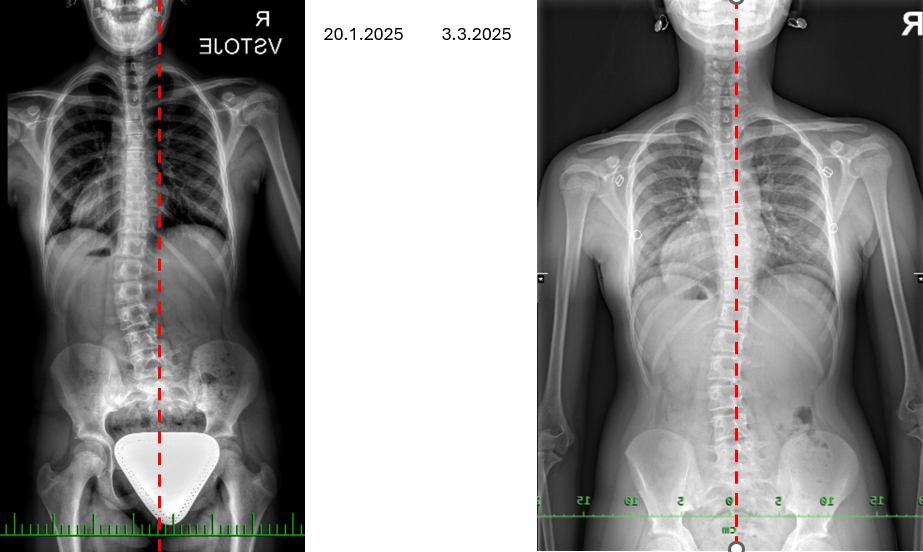

Intenzitu a četnosti schůzek nastavujeme individuálně podle stavu dítěte. Poskytujeme preventivní péči, péči ke zlepšení skoliotické křivky, přípravu před operací páteře i pooperační terapii. Pravidelné cvičení spirální stabilizace zlepšuje skoliotickou křivku, což můžete vidět na obrázku níže. Ne všechny deformity páteře u dětí lze řešit konzervativní cestou. Ale důsledné cvičení spirální stabilizace může zajistit menší rozsah operace a také urychlit rekonvalescenci po operaci.

RTG snímky po 8 měsících cvičení u 15 leté dívky – bohužel s pauzami, přesto viditelné zlepšení křivky.

Při individuální schůzce volíme dle držení těla a RTG snímků individuální plán. Sledujeme vývoj skoliotické křivky v čase. Snímky těla ve spodním prádle jsou pro práci se skoliózou neodmyslitelné. Neslouží pouze pro sledování postupu práce, ale jsou pro naše malé a dospívající klienty velmi motivační. Vždyť každý, kdo cvičí každý den, chce vidět na těle výsledky. Ovšem je riziko asi 10%, že na fotografii může dítě vypadat lépe, ale skoliotická křivka se nezlepšuje. Proto je nutné nechat přes žádanku od ortopeda osnímkovat každých 6 měsíců páteř dlouhým snímkem (tzn. – nejlépe s celou hlavou až pod pánev a na šířku celých paží-viz RTG snímky níže). Vždy ve stoje. Se snímky provedenými v leže nelze efektivně pracovat). Velkou výhodou je také boční snímek, kdy je zřetelné prohnutí páteře a rotace. Ovšem s předpaženými pažemi, které nepřekrývají hrudník.